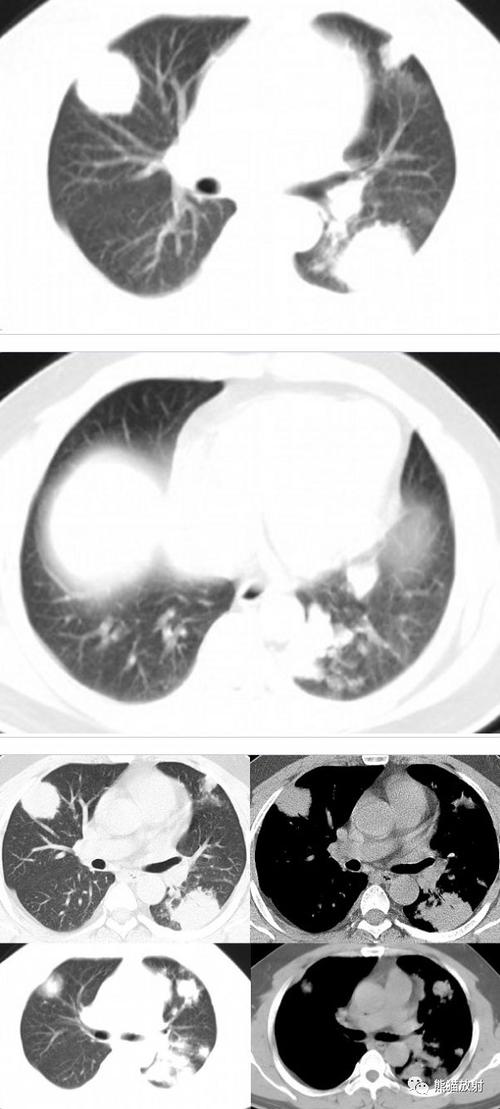

表现为多发结节的肺隐球菌病1例ct影像

ct示两肺多发结节(isobe t, et al. intern med. 2019)